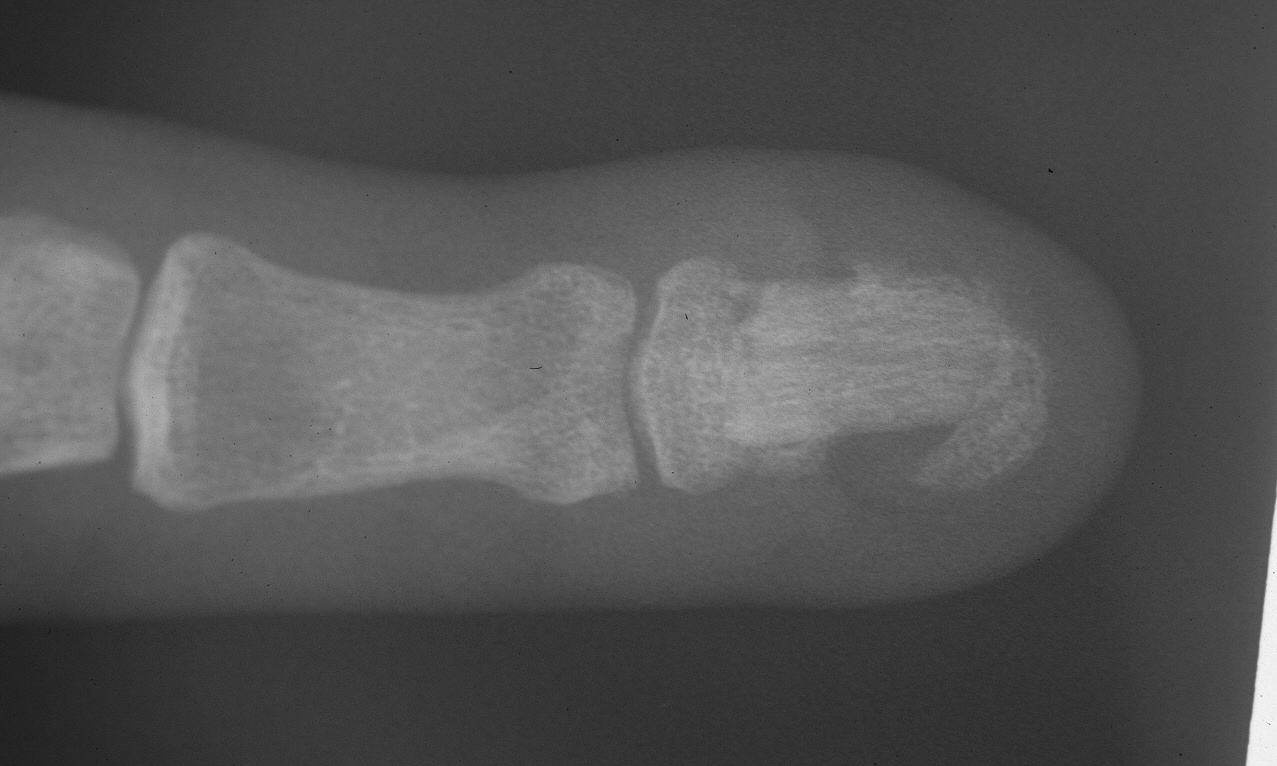

Case 1. This patient had an unstable small fingertip following a saw injury which resulted in loss of the central half of the distal phalanx of the small finger.

After two weeks of distraction: